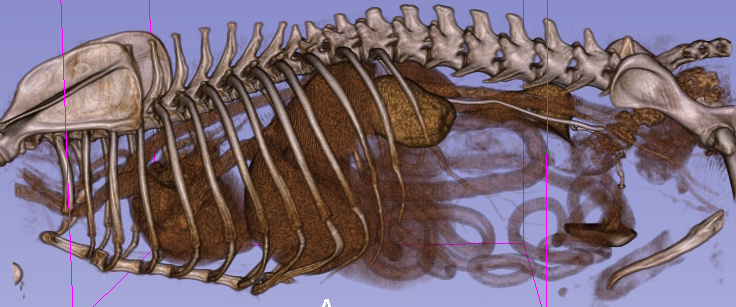

4) Cystic Kidney - incidental abdominal mass palpated during routine health exam

Blaze, 13 yr old chihuahua, was referred for surgery after his primary care veterinarian palpated an abdominal mass during a routine wellness exam. Abdominal radiographs were obtained, and a splenic mass was suspected.

We recommended additional diagnostics to identify the origin of the mass and to check for evidence of metastasis prior to an exploratory abdominal procedure.

Abdominal and thoracic studies pre and post contrast were obtained. Whilst the spleen appeared to be free of disease, the 3D renderings clearly showed a deformed left kidney. Review of the axial images showed a large abdominal mass originating from the left kidney. The right kidney appeared free from disease. No evidence of metastasis was detected within the chest or abdominal lymph nodes. The only abnormalities on lab work included mild elevations of ALT and BUN. Blaze was taken to surgery, where his left kidney was surgically removed. Histopathology confirmed the mass as a benign cystic structure.